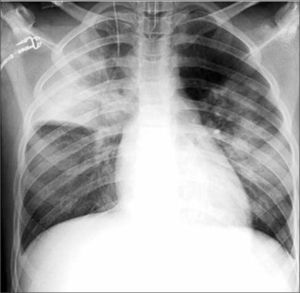

En los niños este compromiso se observa predominantemente en infecciones bacterianas. Desde el punto de vista anátomo-patológico, la neumonía corresponde a un compromiso inflamatorio del parénquima pulmonar en el que los alvéolos, normalmente llenos de aire, se rellenan con detritus y secreciones lo que radiológicamente hace aumentar la densidad del parénquima comprometido; puede ser inicialmente disperso y con escasa tendencia a la focalización, determinando inicialmente opacidades tenues, únicas o múltiples. La consolidación neumónica puede requerir hasta 24 horas para tener una adecuada representación radiológica, por lo que exámenes muy precoces pueden originar falsos (-) en el diagnóstico (4). Cuando el compromiso progresa, se evidencian conglomerados densos que pueden constituir la clásica neumonía lobar o también áreas confluentes, parcheadas, focales uni o bilaterales, descripción que se ha utilizado como equivalente al concepto de bronconeumonía, término que actualmente se considera ambiguo por lo que se recomienda referirse a estas alteraciones como “compromiso alveolar multifocal” (4) (Figura 3).

La persistencia de aire en los bronquios adyacentes a las áreas condensadas produce el signo clásico de “broncograma aéreo” en el espesor del foco denso que aparece surcado por imágenes aéreas ramificadas, imagen que puede también observarse en atelectasias.

En el análisis de las Rx de tórax de los niños es importante observar cuidadosamente los hilios, el área retrocardíaca y las bases pulmonares (proyectadas retrodiafragmáticas en placas frontales), que corresponden a sitios en que se localizan las neumonías denominadas escondidas (Figura 4).